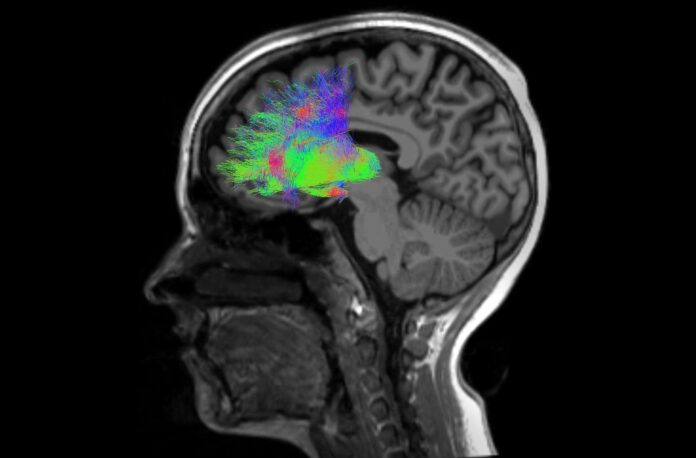

For the study, scientists examined the brains of a total of 171 individuals. This included 85 patients diagnosed with schizophrenia and 86 healthy volunteers (the control group). Magnetic Resonance Imaging (MRI) was used to assess the levels of iron and myelin in specific brain regions.

Analysis of the experimental data revealed iron and myelin anomalies in specific brain structures of individuals with schizophrenia, including the caudate nucleus, putamen, and globus pallidus.

The results showed a decrease in magnetic susceptibility and an increase in mean diffusivity. These findings confirm a reduction in iron and myelin content in these brain regions during schizophrenia.